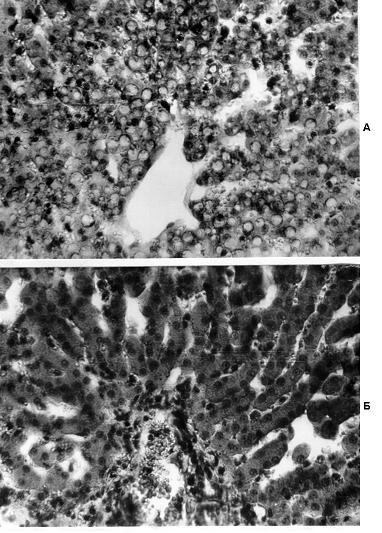

Рис. 6. Структурные изменения в печени у кошек при

геморрагическом шоке и их

коррекция липосомами

А – печень кощки. Геморрагический шок. Жировая и вакуольная

дистрофия, запустение центральных вен и синусоидов.

Б – печень кошки. Геморрагический шок + липосомы через 70 мин после

инокуляции. Отсутствие проявлений жировой и вакуольной дистрофии; уменьшение

признаков отека; в просвете синусоидов встречаются форменные элементы крови.